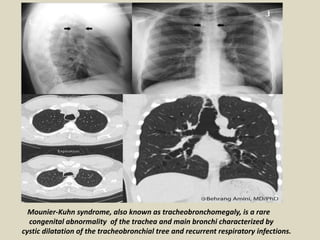

Mounier-Kuhn's syndrome. Enlarged mainstem bronchi

(black arrows) and distal bronchiectasis (white arrows).

Mounier-Kuhn syndrome, also known as tracheobronchomegaly, is a rare

congenital abnormality of the trachea and main bronchi characterized by

cystic dilatation of the tracheobronchial tree and recurrent respiratory infections.

Mounier-Kuhn Syndrome. Two axial CT images of the thorax demonstrate marked dilatation of the

trachea (T) and right (R) and left (L) main bronchi in this patient with Mounier-Kuhn syndrome. Notice

the bronchiectasis (red arrows and red circle) in which the bronchi are larger than their accompanying

blood vessel and there is tram=tracking of thickened bronchial walls seen in profile.